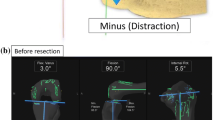

The femoral rotational axis was defined as being perpendicular to the Whiteside line. The tibial rotational axis was set parallel to the line connecting one-third of the tibial tubercle to the centre of the cut surface. Anchoring pins with an infrared signal transducer were fixed into the femur and tibia as reference points, and the joint capsule was temporarily closed with four strands of suture after registration. The investigator gently applied physiologically allowable maximal manual internal and external rotation stress to the knee without angular acceleration, and the mechanical femoral–tibial rotational angle was measured automatically by the navigation system at 30°, 45°, 60°, and 90° of knee flexion. The measurements obtained directly following joint-capsule closure, with the presence of osteophytes, soft tissues, meniscus, and the cruciate ligaments, were defined as the pre-operative record. The articular surfaces of the distal femur and the proximal tibia were resected using the navigation-assisted measured resection technique. The largest sized components without both anteroposterior and mediolateral overhang were selected, after utilising the femoral-sizing guide and tibial-sizing plate. After trial components were placed, the medial–lateral balance of the knee was assessed throughout ROM. When the soft tissue balance was inappropriate, a minimal-released stepped adjustment was applied for accurate ligament balance as necessary: the release of medial collateral ligament, posterior knee capsule or PCL, or bone additional resection.

After confirming that the TKA components and inserts were firmly placed in an appropriate position, the surgical incision was completely closed. Thereafter, the same procedure as described for the pre-operative measurements was repeated to measure and record the rotational angles at 30°, 45°, 60°, and 90° as post-operative rotational laxity. Total rotational laxity was recorded as the sum of the absolute internal and external stress angles. Positive values indicate internal orientation, and negative values indicate external orientation. The accuracy of the navigation system has been established at 0.5°.